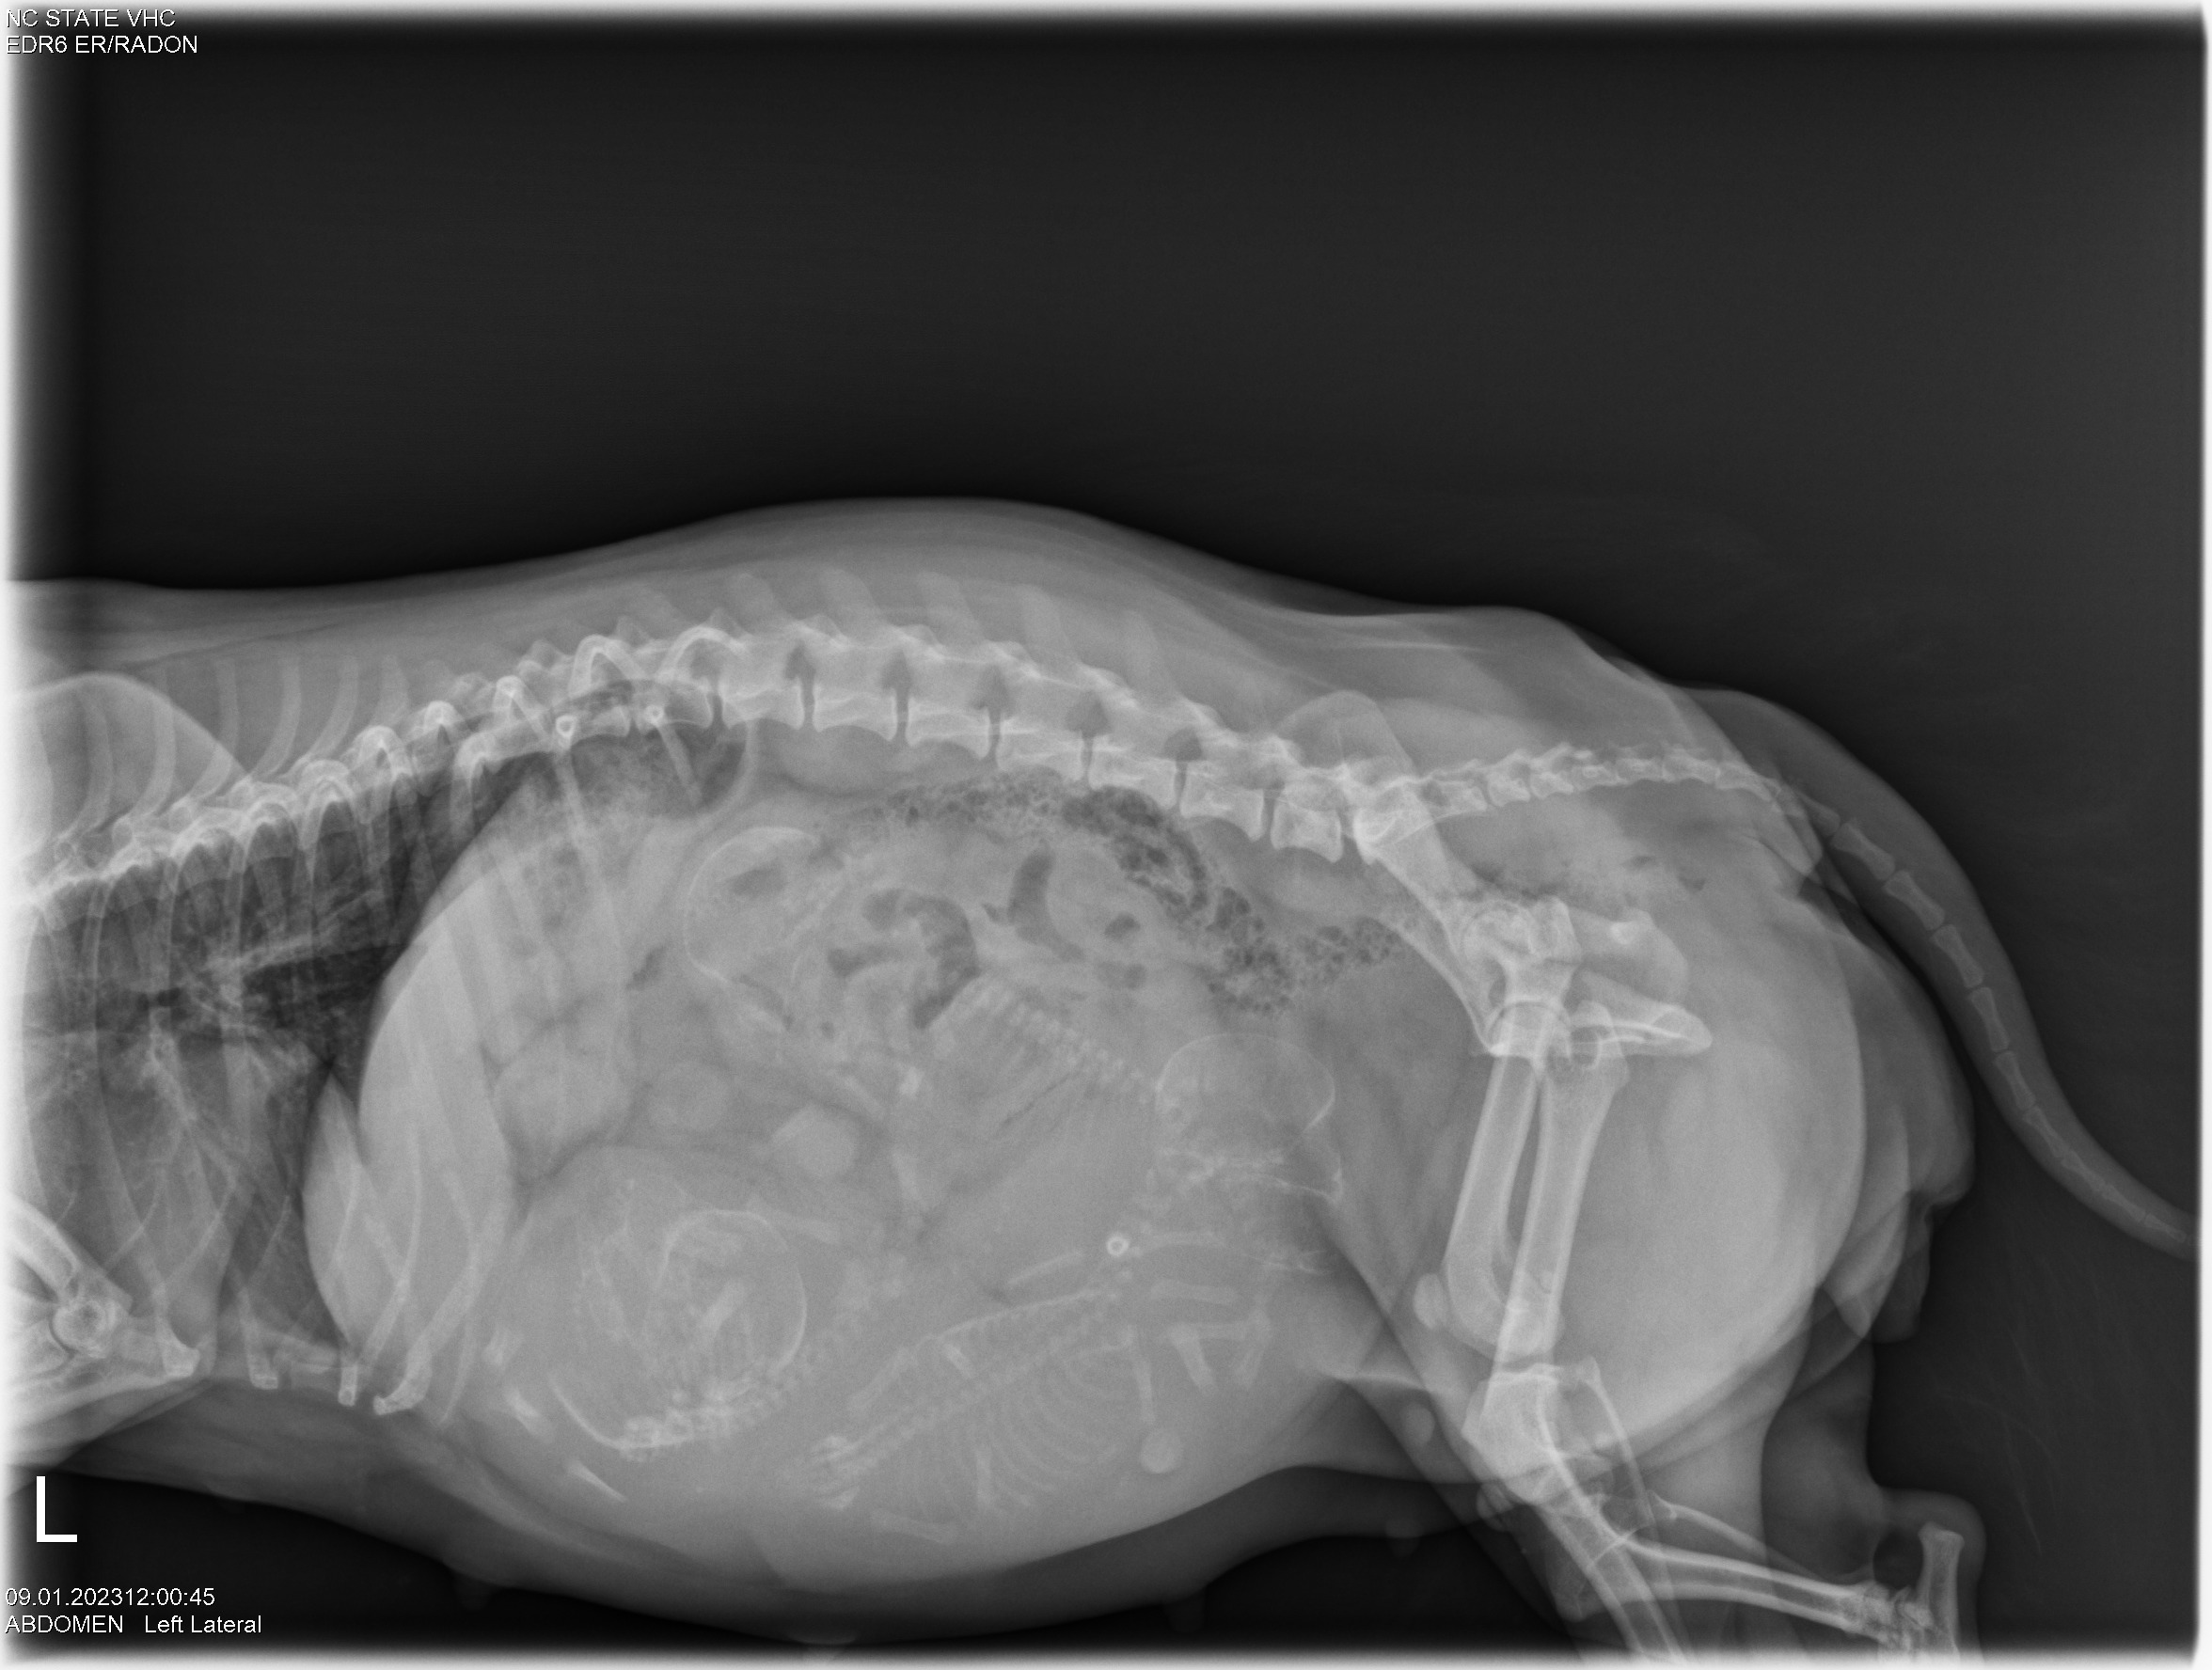

Today was x-ray day! I took both Gwynie and Siri to NC State University for abdominal x-rays. Here they are: (If you look closely, you can see the spines and perhaps the skulls of the puppies.)

Looking at the x-rays, my repro vets told me that Gwynie is carrying three puppies, and Siri is carrying two. Comparing the size of the pelvic opening of each girl with the size of the puppy skulls they are carrying, I was told for both Gwynie and Siri that the sizes are close. I was advised to have a cesarean section (c-section) for both girls. So that is what we will do.

Since Gwynie's due date is this weekend, the vets started "staging" Gwynie for a c-section. The vets checked out Gwynie's puppies using ultrasound and all looks good - good heartbeats and good GI motility. They took some blood from Gwynie and did a progesterone test. Towards the end of pregnancy, progesterone falls. Using the ultrasound results and progesterone number lets the vets decide when to do a c-section. Gwynie and I will now come back to NC State (a two-hour ride one-way) each morning for progesterone testing and ultrasound until the vets say "today is the day" for the c-section.